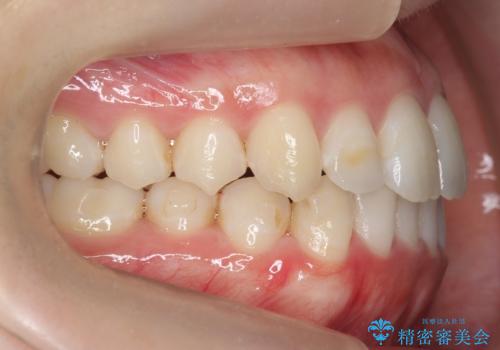

下の歯のがたつき 上より気になる

- 前歯のがたつきが気になって来院。

下の歯のがたつきが上よりも多い状態でした。

下の前歯は上の歯の内側にあるため、外に並べることができないため、上ほど簡単ではありません。

すき間をしっかりとって並べる必要があります。

今回は、下の歯を健康に支障が出ない範囲でわずかに削合し、並べるようにしました。(ディスキングといいます)

前歯のがたつきもしっかり治り、喜んでいただけました。